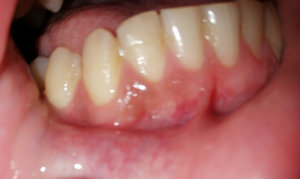

Восемь дней назад удалили нижнюю шестерку. Удаление было сложное, т.к. зуб был гнилой и ломался. Наложили шов и сказали, что его снимать не надо - "сам отпадет", и всё, что нужно делать - не мешать языком заживлению. Боль была сильная и отек не спадал, на пятый день пошла к другому врачу. Сказали, что внешне воспаления нет, а вскрывать жалко, прописали найз на три дня и ванночки настоя ромашки или хлоргексидина. Всё делаю, отек немного спал. Но соседняя пятерка всё еще болит и немного шатается, хотя недавно пломбу ставили, и всё хорошо было. Ещё какой-то неприятный привкус во рту стал, вроде кисловатый.

В некоторых случаях стоматологи используют саморассасывющиеся швы, в этом случае снятие не требуется. Что касается подвижности пятого зуба, скорее всего, доктор имел неосторожность и упирался, при удалении, на пятый зуб и тем самым нарушил его устойчивость. Неприятный запах и привкус возможен. Не переживайте и покажитесь врачу. В будущем в хирургии обращайтесь к более опытным докторам.